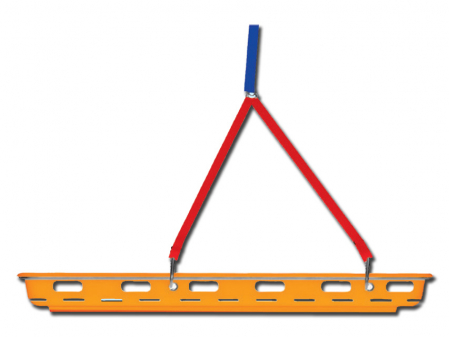

Nanotubul este un debitmetru cu bilă pentru administrarea oxigenului sau a aerului medical la pacienții cu insuficiență respiratorie.

Utilizează rezultatele programului de cercetare și dezvoltare al companiei. Poate fi conectat la o unitate terminală de perete, direct sau indirect, printr-o clemă și un sistem de montare a șinei.

Conexiuni: AFNOR, DIN, BS, UNI, Ohmeda

Disponibil cu sonda NF click-fit

Fiabil și sigur (disponibil în versiunea compatibilă MR)

Construcție robustă și durabilă

Ușor de instalat și utilizat

Material: Alamă și copoliester placate cu nichel

Dimensiuni: 165(H) x 90(L) x 30(h) mm (cu sondă NF)

Greutate: 289 g

Precizaie: ± 10 % din valoarea afișată

Diametrul filtrului de intrare: 40 µm

Variante: 0-1 L/min, 0-5 L/min, 0-7 L/min, 0-15 L/min, 0-30 L/min, and 0-70 L/min